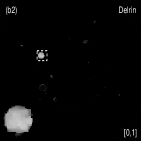

Fig. 4 shows the decomposed material images by the Direct Inversion, the PWLS-EP-LOOP and the PWLS-TNV- method. The left corners of the to the column of Fig. 4 show enlarged rods that are highlighted with white dashed boxes in decomposed material images. Table 2 summarizes the means and noise STDs of ROIs of decomposed basis material images. The volume fraction (VF) accuracies were , , and for the Direction Inversion, the PWLS-EP-LOOP and the PWLS-TNV- method, respectively. Compared with the Direct Inversion and the PWLS-EP-LOOP method, the proposed PWLS-TNV- method increases the VF accuracy by and respectively.

Table 3 summarizes the average electron densities of contrast rods and RMSE() of electron density for the three MMD methods. The RMSE() was , and for the Direct Inversion method, the PWLS-EP-LOOP method and the proposed PWLS-TNV- method, respectively. The proposed PWLS-TNV- method suppressed noise, decreases crosstalk and increased decomposition accuracy in the material images, while maintaining high image quality.